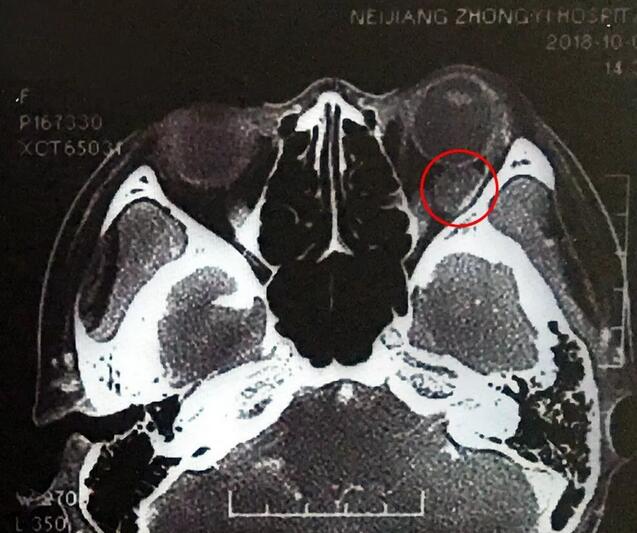

小何是四川南部县人,今年20岁,在内江上大学。今年9月底开始,出现头痛、反复呕吐,吐得连药都吃不下。医生建议小何做了脑部CT,“结果显示左眼眼球后部有个东西,经过进一步检查竟是肿瘤!”这对小何来讲真是个晴天霹雳。

在成都牛八体育,经过详细检查,罗清礼教授根据他40余年的丰富经验,判断为淋巴血管瘤。“现在,虽然她双眼的视力都是1.0,但是眼内肿瘤已经接近眼球那么大了,若不及时手术必将失明。”

罗教授介绍,淋巴血管瘤早期症状并不明显,“一般人感冒是不会头痛、呕吐的。小何的感冒非常幸运,她感冒后引起淋巴增生,导致肿瘤内出血,然后引起了头痛、呕吐等症状,让她能够尽早发现了肿瘤。”患者的肿瘤体积较大,位置较深,位于眶间且紧挨着视神经,手术稍有差错,就可能导致患者视力丧失、大出血等情况发生。得知手术风险后,患者和家属表示非常理解并信任罗教授,坚决要求手术医治。